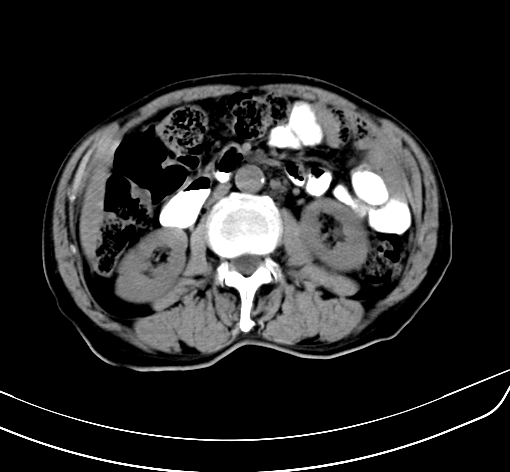

病人 男 70 咳嗽 胃部不适 2月余

胆囊壁增厚,与临近肝实质边界不清,临近肝实质内可见大片边界不清之低密度区,肝门区密度亦有减低,部分结构不清,尾叶前方可见块状影,肝右叶可见多枚边界不清之圆形低密度区,肝内胆管扩张征象,结合病史考虑1胆囊癌肝内转移,肝门区淋巴结转移,门脉癌栓待排2肝内胆管扩张3建议增强扫描

肝脏多发大小不等低密度灶,边界不清,肝门区结构不清,肝内胆管轻度扩张,胆囊密度不均匀,内见软组织样密度影,与相临肝脏边界不清.考虑:1、胆囊ca侵犯肝脏并肝内多发转移,肺上也有结节影,转移?建议强化扫描.2、胃充盈不好,如怀疑有病变最好建议做相关检查.

胆囊壁增厚,周围模糊不清,肝内多发低密度影,胃充盈欠佳,胃壁增厚,外形尚规整,考虑胆囊炎、胆囊癌肝内转移?建议胃肠道进一步检查或增强扫描。